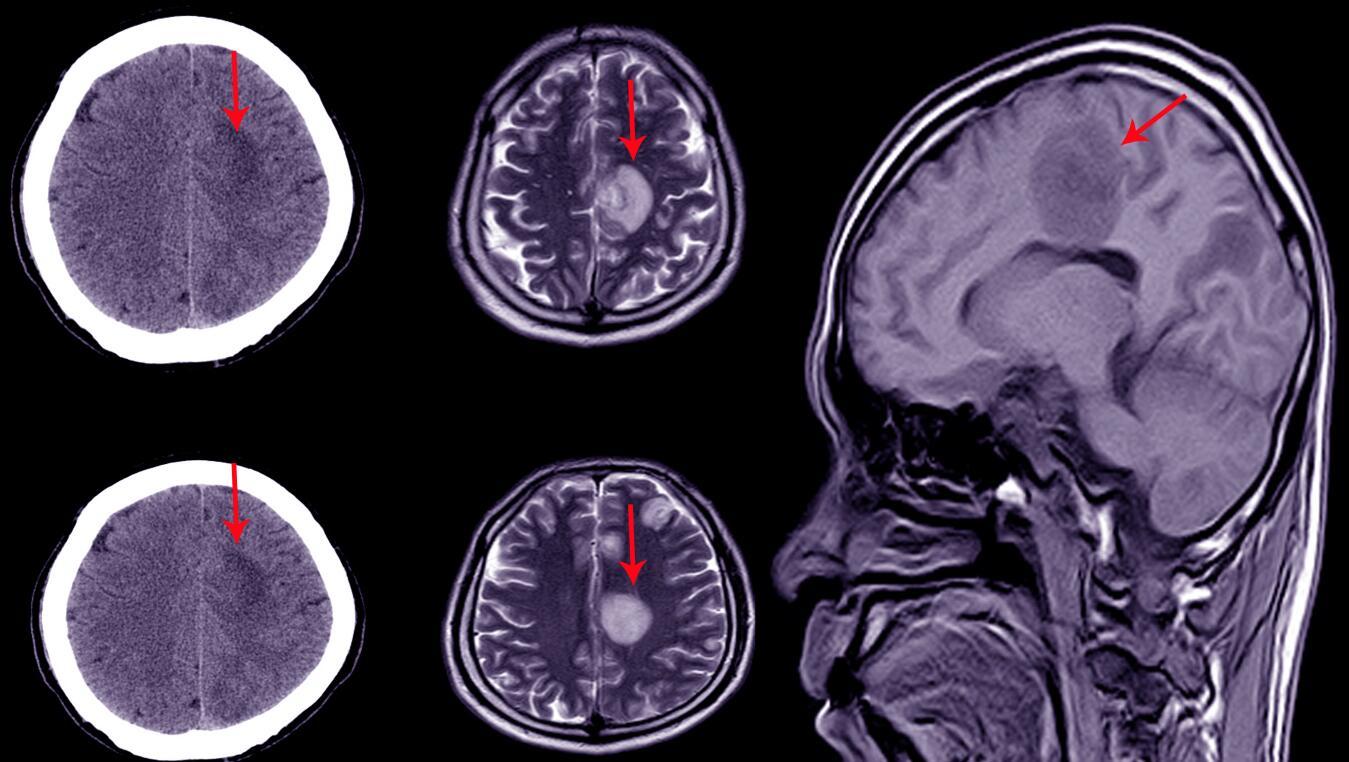

生殖细胞瘤最常见的诊断手段,首先是要进行头颅的CT和磁共振的扫描,通过这些影像学的表现,可以直观地看到位于不同的病变区域,比如鞍区、松果体、基底节区的一些异常信号,来明确肿瘤的存在。